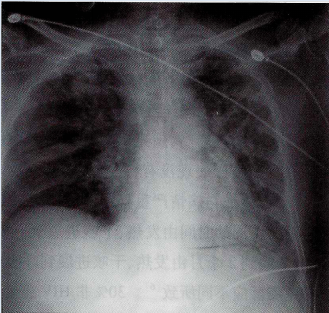

3月3日复查床旁胸部X线片提示双肺病灶逐渐吸收好转图4

图4  2016年3月3日胸部X线片:双肺少许斑片状阴影

3月16日复查胸部CT:双肺少许磨玻璃密度及索条阴影,2月15日病灶明显吸收图53月18日患者后好转出院。

图5  2016年3月16日胸部CT:双肺少许磨玻璃影及斑片状索条影